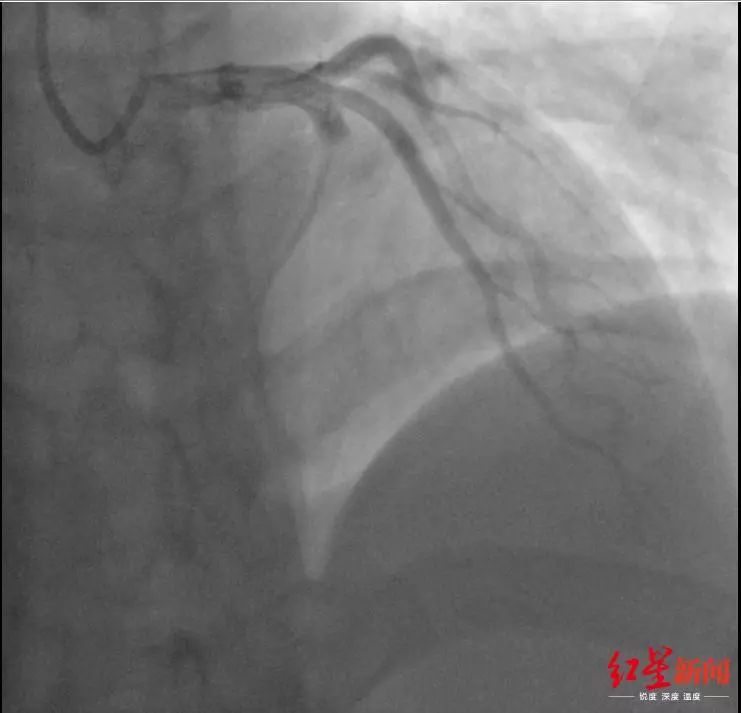

心梗!医生:日常生活“微”信号可以看出端倪!